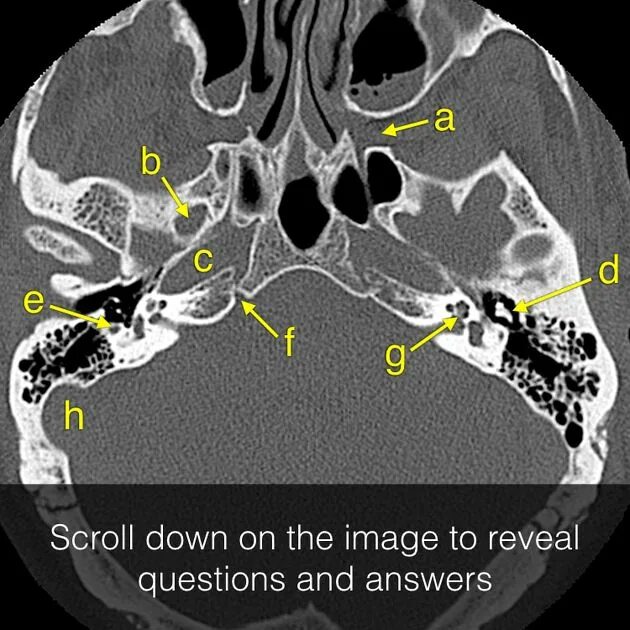

Череп на кт